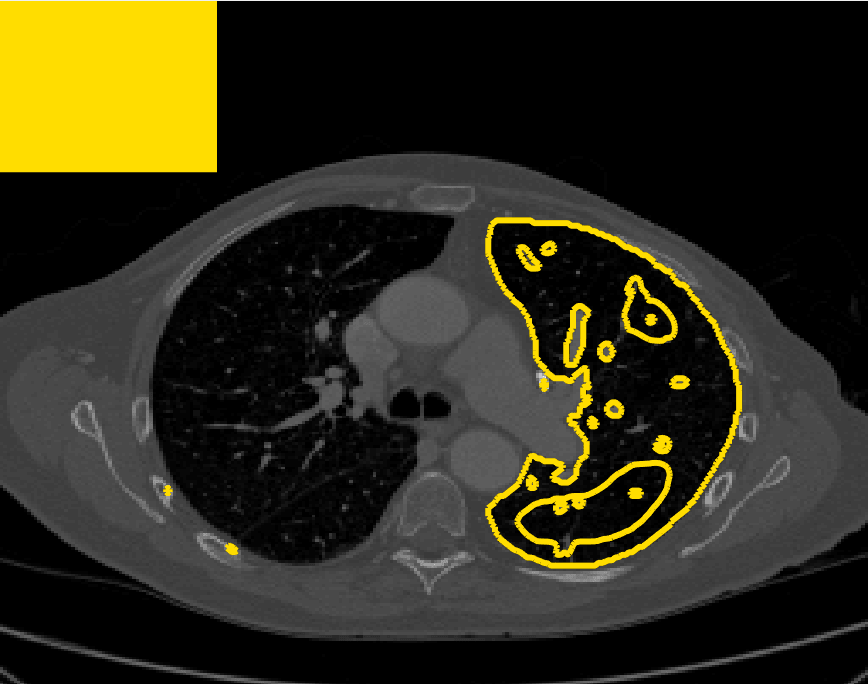

Test Images. We will perform initial tests on the images shown in Figs. 5–7. We have provided the ground truth and initialisation used for each image. Test Images 1–3 are synthetic, Test Image 4 is an MRI scan of a knee, Test Images 5–6 are abdominal CT scans, and Test Images 7–9 are lung CT scans. They have been selected to present challenges relevant to the discussion in §2. We focus on medical images as this is the application of most interest to our work. In the following we will discuss the results in terms of synthetic images (1–3) and real images (4–9). We also test the proposed approach on a larger data set of 30 CT images (a sample of which is presented in Fig. 18), comparing against existing selective methods detailed in §3.

Real Images. In Fig 12 we present results for Test Images 4–6. Here, the proposed model performs in a similar way to its competitors because these images are more typical selective segmentation problems in the sense that there is a clear distinction between the foreground and background intensities. In particular, the values in each case are: Test Image 4 , Test Image 5 , and Test Image 6 . It can be seen that the proposed model is competitive compared to previous approaches. The performance is quite poor for Test Image 5, but is arguably still the best for this challenging case. In Fig. 13 we present results for Test Images 7–9. Here the proposed model outperforms previous approaches significantly for each image. This is mainly due to the type of image considered. Specifically, the true intensities are: Test Image 7 , Test Image 8 , and Test Image 9 . The proposed model is capable of achieving results where , with other models failing completely in these cases.

Real Images. In Table 1 we can see that the proposed model is the most successful in terms of optimal accuracy. It is worth noting some inconsistency in the other models, with all but GAV having results that fall below TC for at least one image. GAV performs well for Test Images 4–9, with the proposed model slightly outperforming it in each case. It is worth reminding the reader that for GAV the parameters have been refined for each example. Fixing this results in more variability in the quality of results. The proposed model has no such parameter optimisation between examples. CAC and SRW perform reasonably well for these images, although are sometimes substandard for Test Images 4-7. This is despite extensive refinement of the user input to achieve an acceptable result. We present the optimal results for Test Image 9 in Fig. 14. Here we can see how much variation there is in the quality of results for this lung CT image. CAC and SRW are competitive in this instance. Of the remaining approaches GAV is the most competitive (TC ), but is visually inadequate. Two other models (CV, HYB) fail completely. In this case, the problem looks quite straightforward and yet other fitting terms are insufficient to produce a good result. Again, the proposed model tends to be superior in cases where and is capable of achieving very good results for all the images considered. This highlight the advantages of the proposed fitting term.